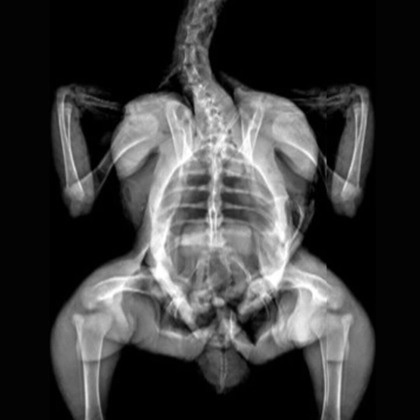

Marmosets. Image Credit: Scintica Instrumentation Inc

X-Ray Attenuation Image - Rat. Image Credit: Scintica Instrumentation Inc